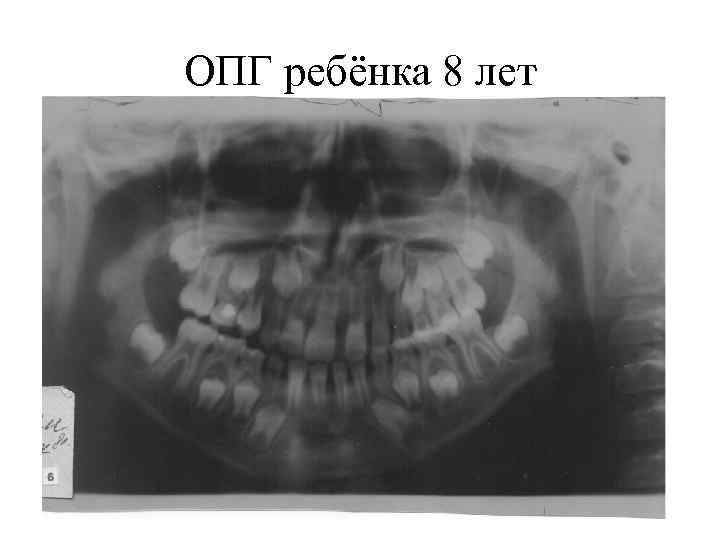

ОПГ ребёнка 8 лет